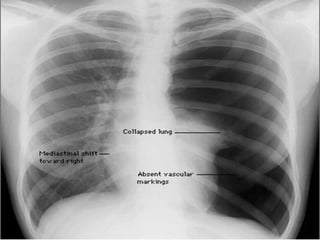

Chest x ray

Shows : increased radiolucency, with

absence of bronchovascular markings

• extend of mediastinal shift.

• pleural fluid ,if present .

• underlying pulmonary disease .

• (costophrenic angles are clear)

Investigations Chest x ray Shows: increased radiolucency, with absence of bronchovascular markings • extend of mediastinal shift. • pleural fluid ,if present . • underlying pulmonary disease . • (costophrenic angles are clear)